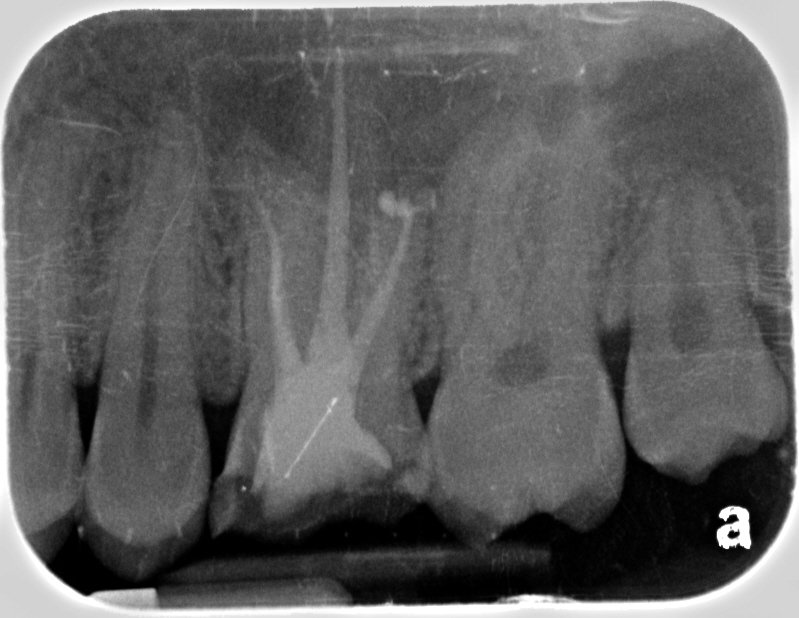

Completed in Mendota. First photo is CaOH. Second and third is final fill. The film quality limits ability to see the MB2 here.You can see more dense fill where the MB2 overlaps MB1 ending about 3mm from apex.